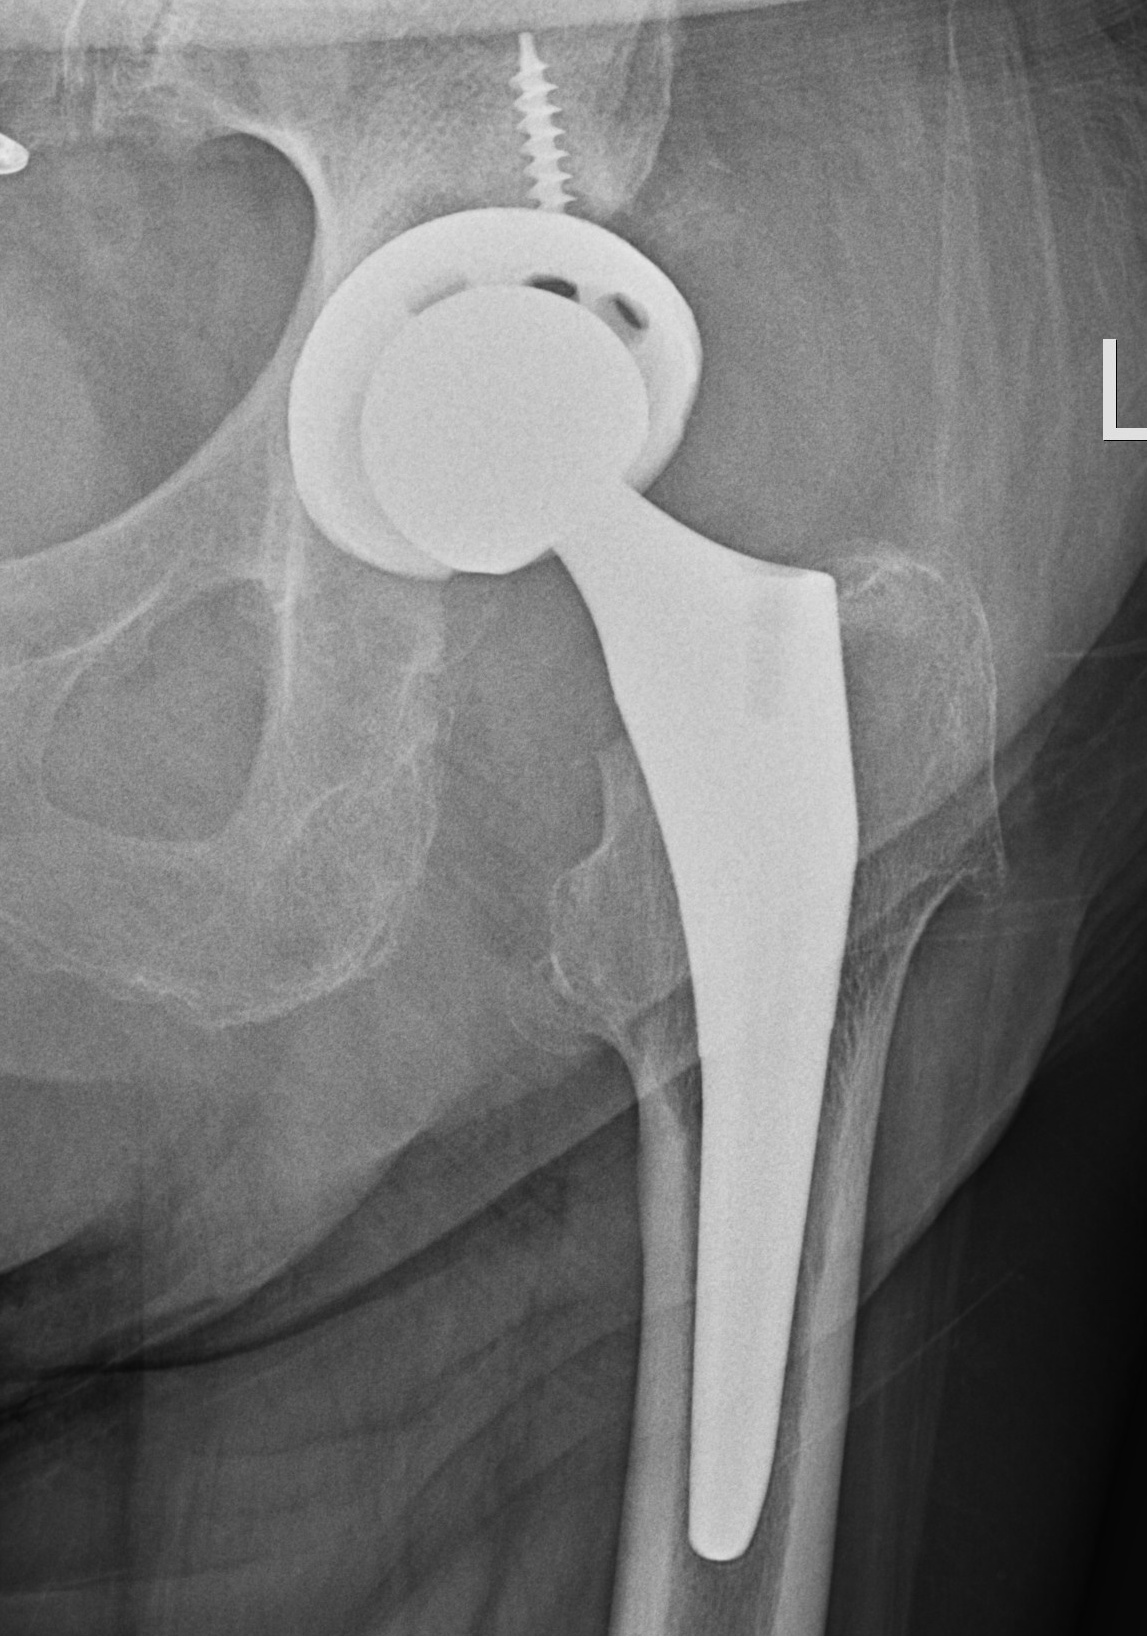

X-ray

1. Progressive radiolucent lines / rapid lysis

2. Focal osteolysis with endosteal scalloping

3. Periosteal new bone

- pathognomonic of infection

- usually at junction meta / diaphysis on medial side

- uncommon

Femoral stem lysis Acetabular lysis